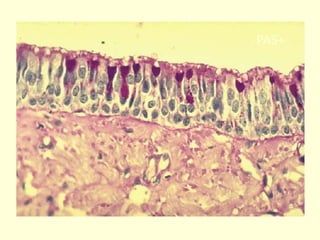

Esófago

Traquea

PAS+

 La pared traqueal está compuesta por:

• Mucosa, compuesta por un epitelio

pseudoestratificado cilíndrico ciliado con células

caliciformes (epitelio respiratorio) y una lámina

propia con fibras elásticas abundantes.